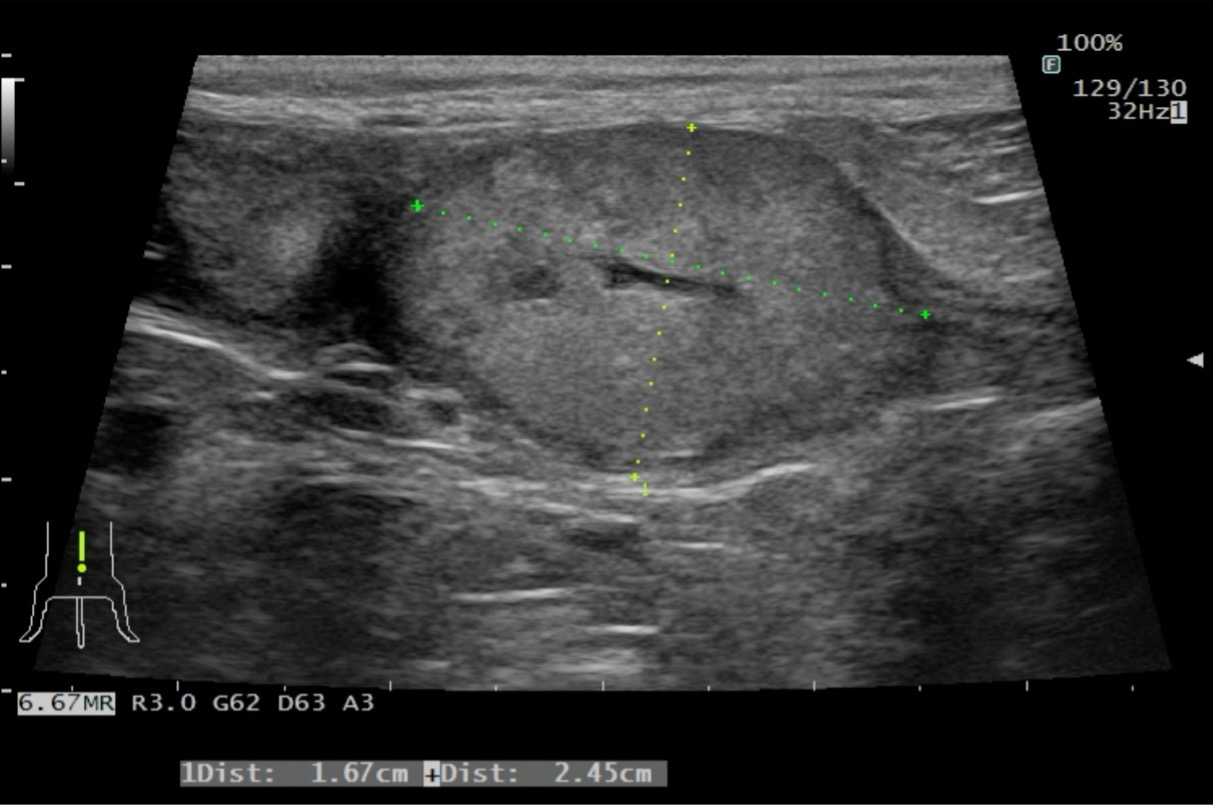

膀胱移行上皮癌の犬の1例

はじめに 犬の膀胱腫瘍の多くは悪性であり、その中でも移行上皮癌が80%と最も多い。症状としては血尿や頻尿、排尿困難など一般的な膀胱炎と同様の症状がみとめられる。病理学的悪性度にもよるが、一般的に根治は困難であり、周囲…